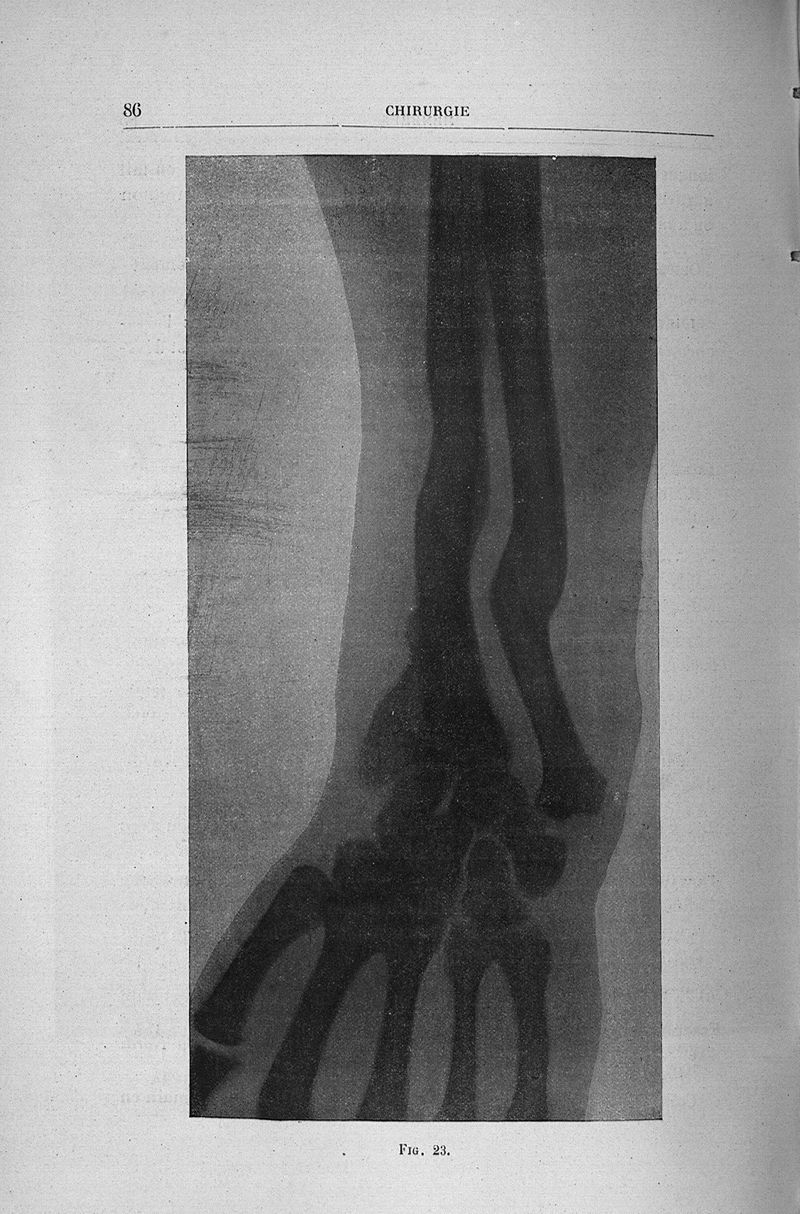

Vanverts, Julien Louis Joseph.

Titres et travaux

Paris, G. Steinheil, 1910.